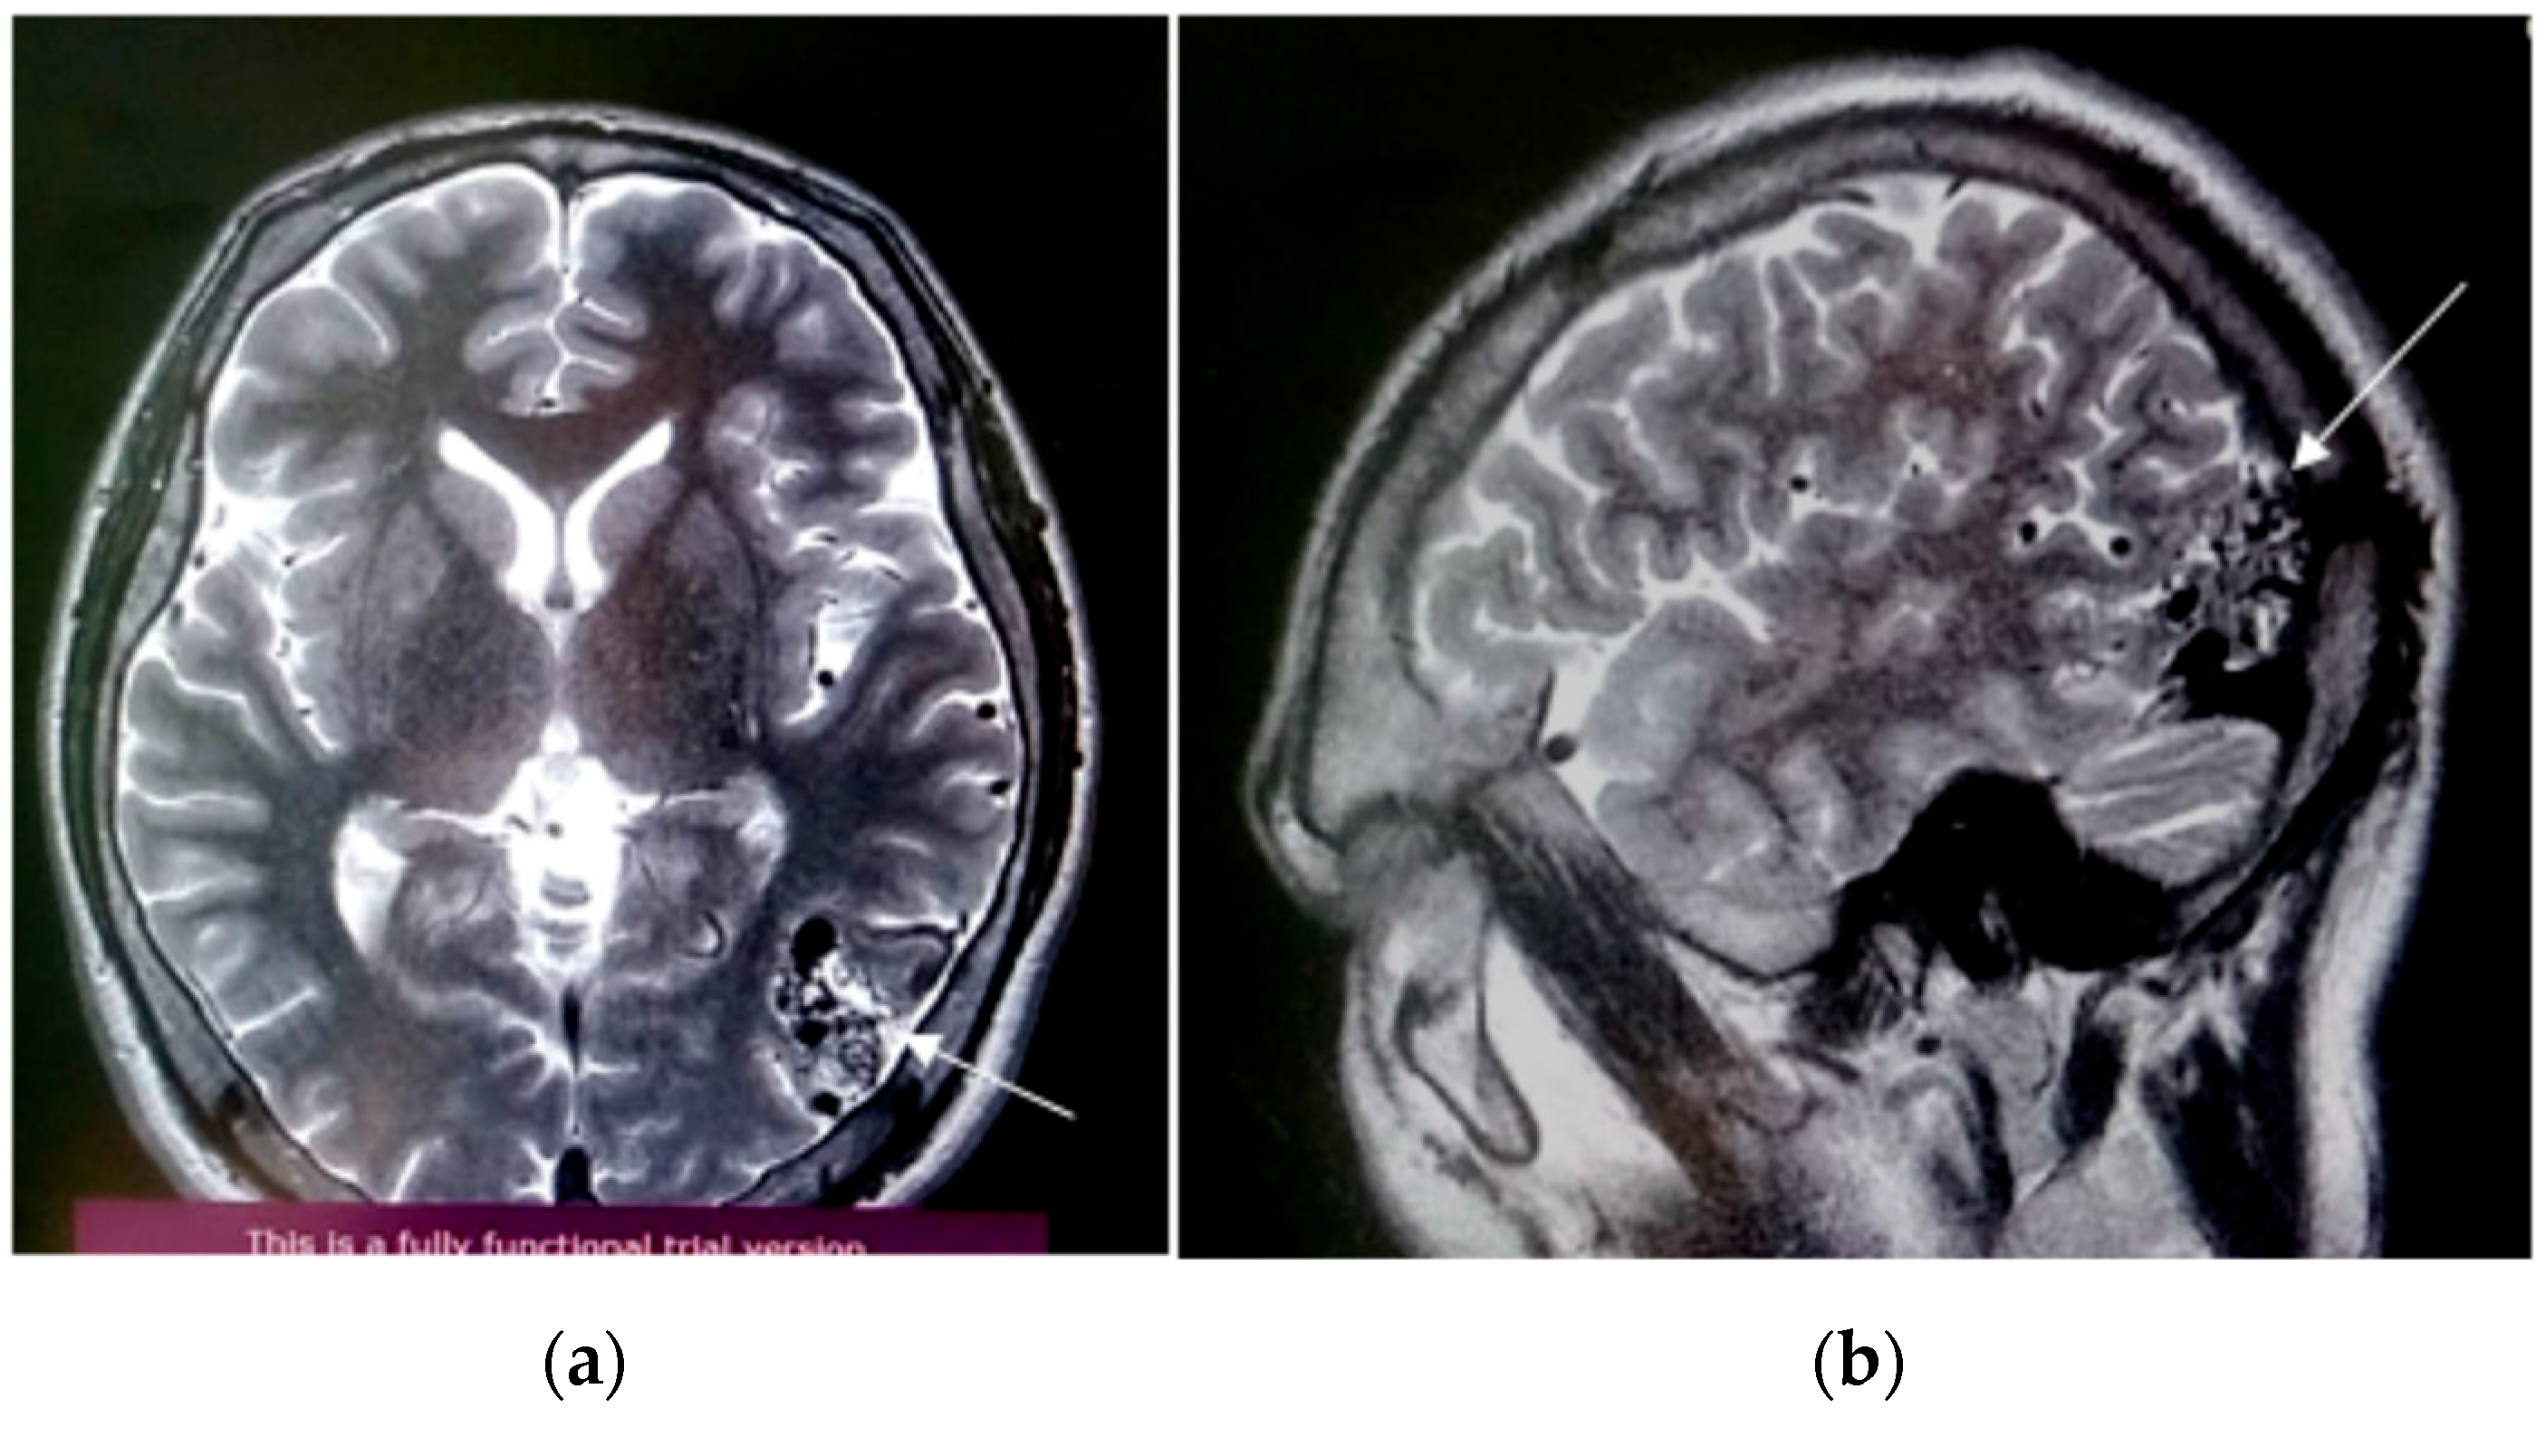

3.1. Case Presentation and Surgical Procedure